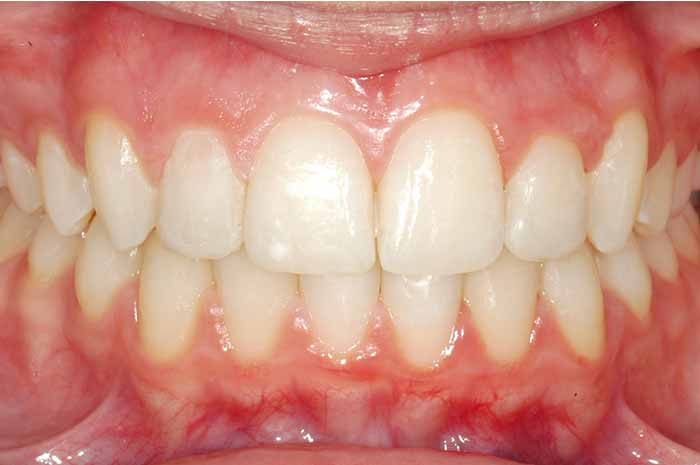

Tratamiento realizado:

Ortodoncia convencional con brackets metálicos

En este caso, para conseguir un resultado óptimo, también se utilizó un aparato removible (de quita y pon) en la arcada superior, previo a la colocación del aparato fijo (brackets).

La excepcional colaboración de la paciente fue fundamental para la consecución de los resultados.

Antes y Después